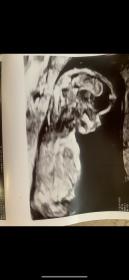

These are from my NT scan at 12 weeks 6 days but I was measuring (and have been) later at 13 weeks 3 days.

I’m driving myself crazy with this one. Do you guys see a nub??

I don’t see a nub

No nub but boy based on skull theroy.